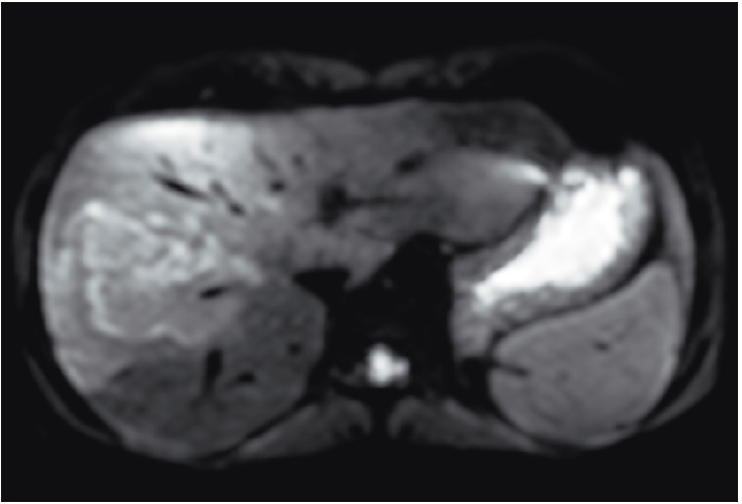

Figura 2b. Imagen de resonancia magnética ponderando la secuencia de

difusión con valor b alto, que demuestra una restricción aumentada en forma moderada en la lesión,

hallazgo que se traduce en hipercelularidad